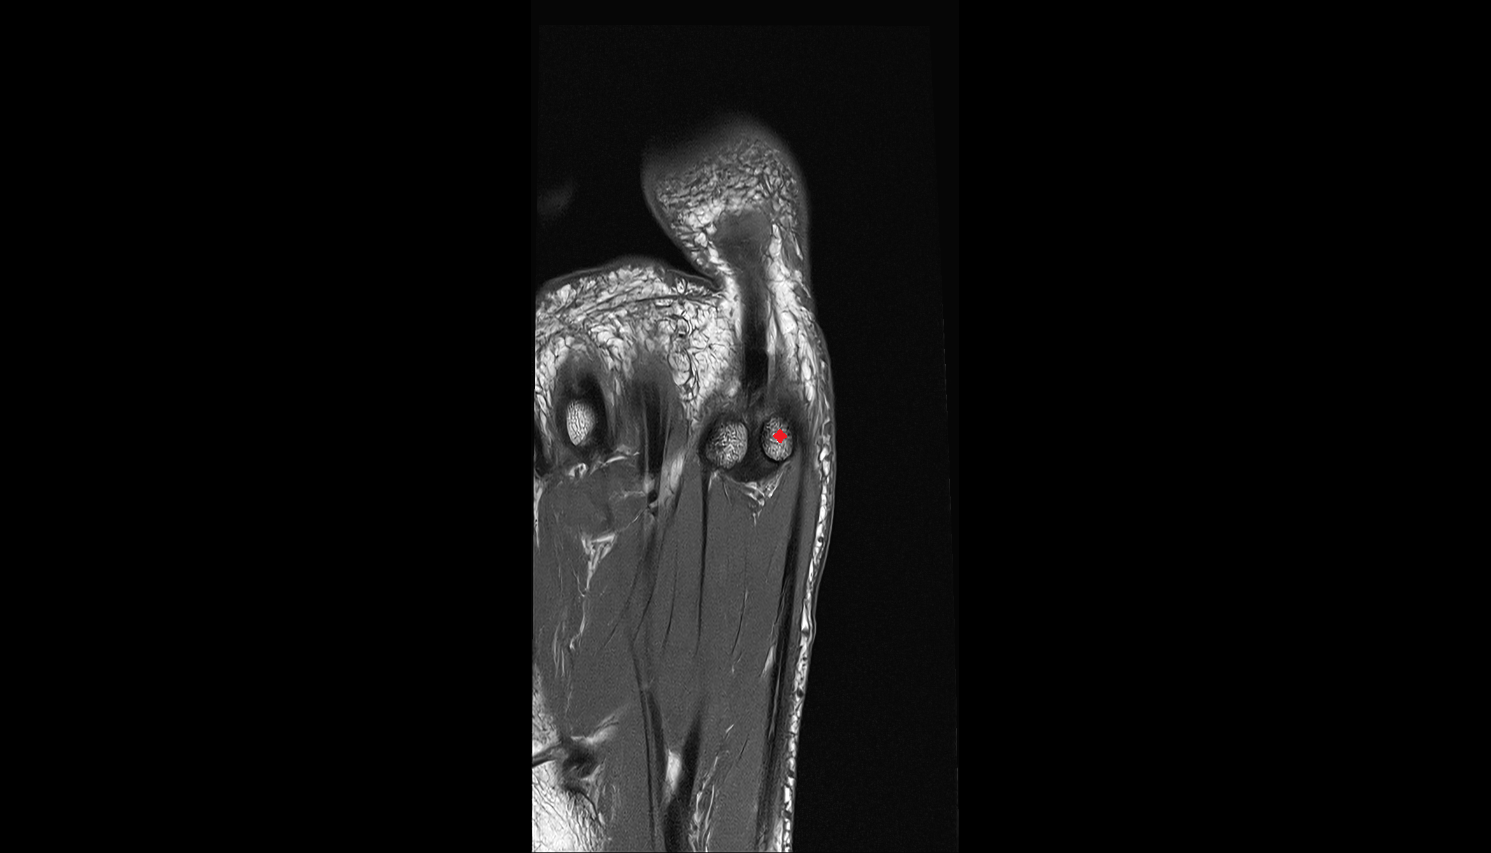

- Sesamoid bone of great toe

- Lateral sesamoid bone

- Medial sesamoid bone

- Proximal phalanx of great toe

- Distal phalanx of great toe

- Metatarsophalangeal joints

- Plantar plate ligament